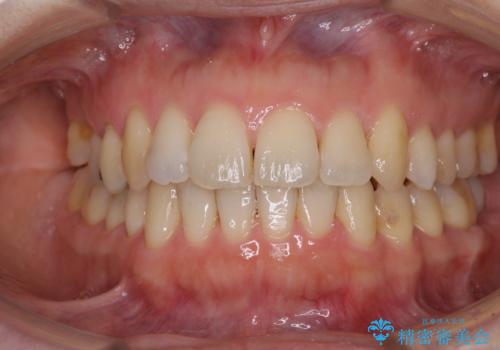

- 上下奥歯の欠損を気にして来院された患者様です。

以前矯正した後戻りにより前歯に叢生が認められたため、矯正治療の提案をしたところ、補綴治療と合わせて矯正治療を行うこととしました。

後戻りの程度は軽度であったため、インビザライン・ライトを用いて歯列を整えました。